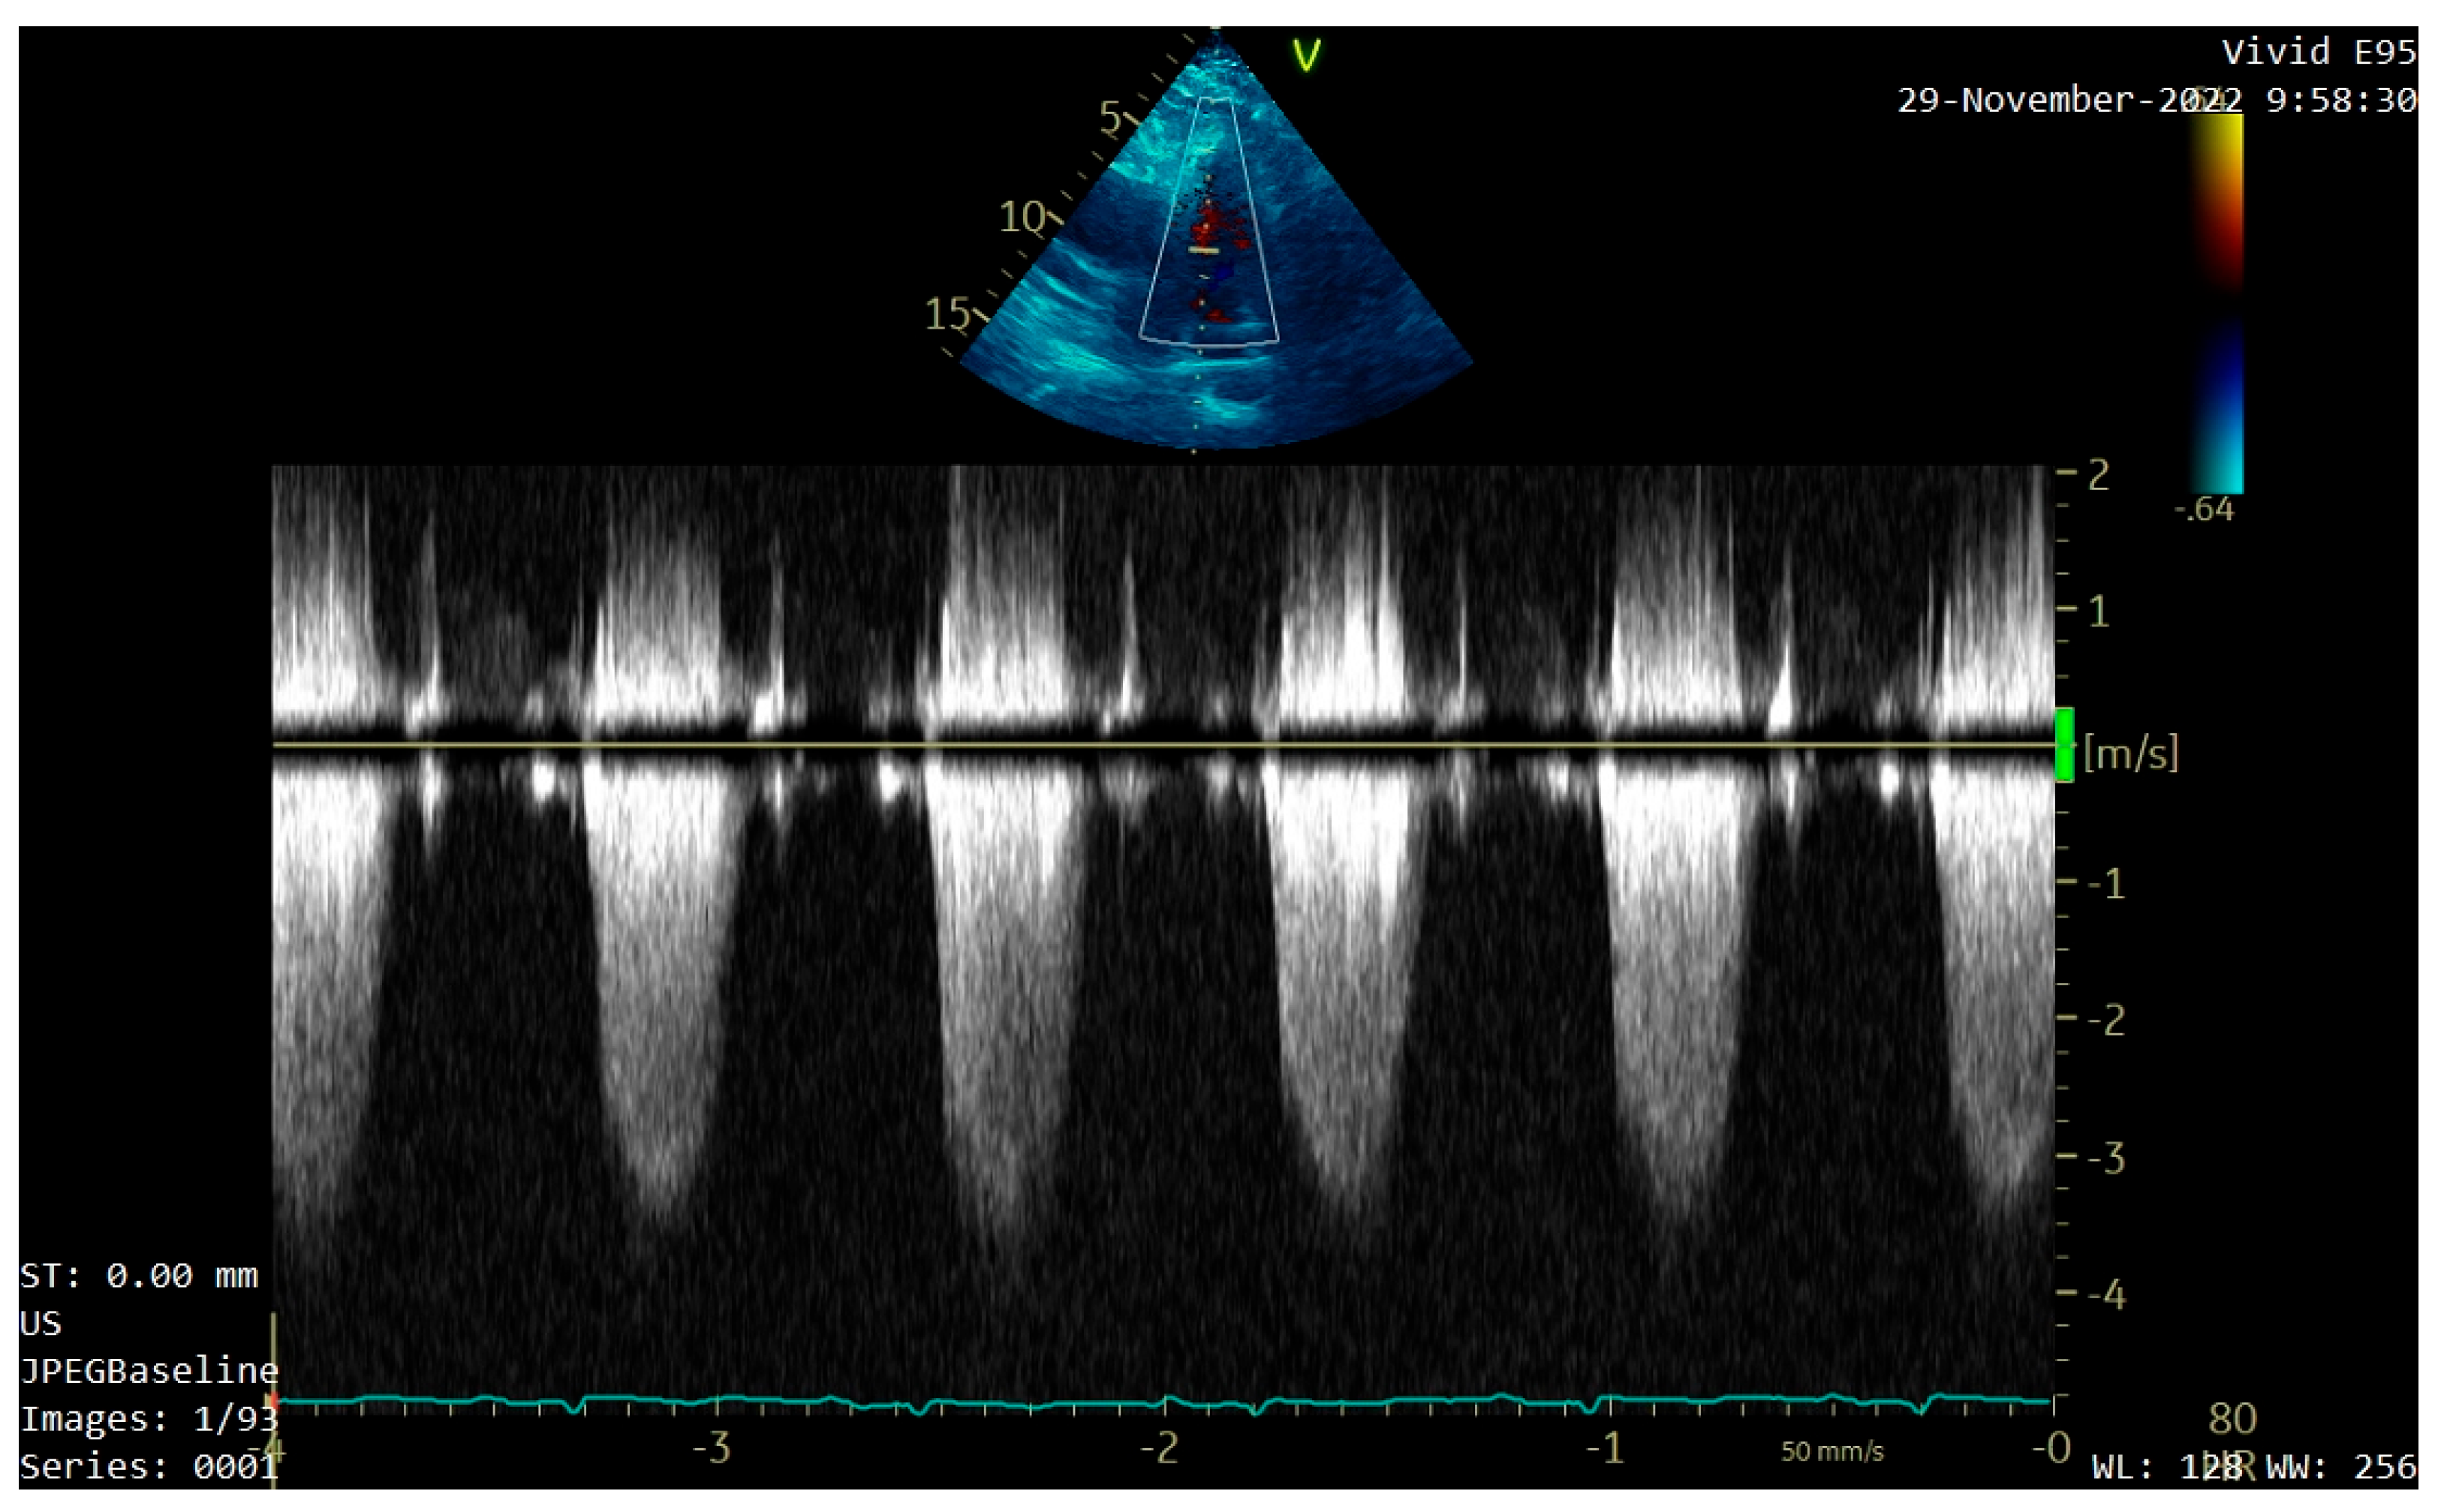

For a better evaluation of the tumor, transesophageal echocardiography (TEE) was performed. It confirmed the location, size, and shape of the tumor, describing it as having low echogenicity, with a similar texture to the myocardium (Figure 3). Comparable pressure gradients at the pulmonary valve were recorded, and patent foramen ovale was identified.

Figure 3. Transesophageal echocardiography (TEE) confirming the location, size, and shape of the tumor (white arrow).